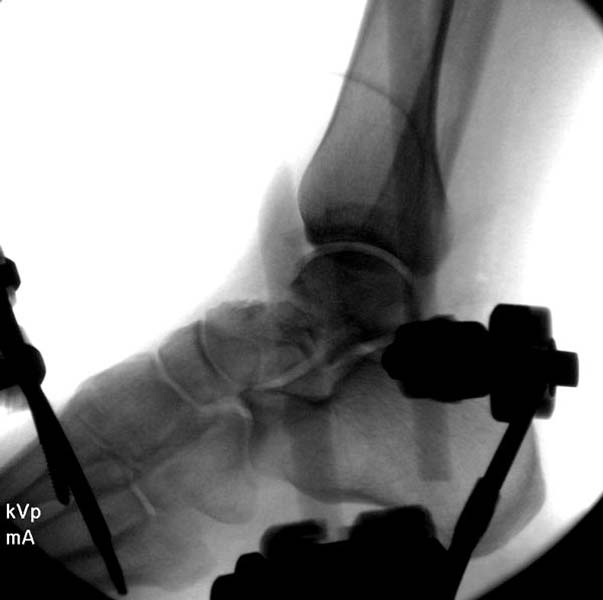

> Больная стабильная после хирургических мероприятии и получив добро,

> приступили к закрытому вправлению таранной кости с укладкой наружного

> фиксатора. Затем укладка больную на бок и открытый остеосинтез

> После спадения отека на стопе произведена фиксация тарана. Кстати, коллеги

> пересмотрели первоначальную консультацию по позвоночнику и на двух уровнях

> провели фиксацию. Из-за длительного постельного режима без нагрузки таз не